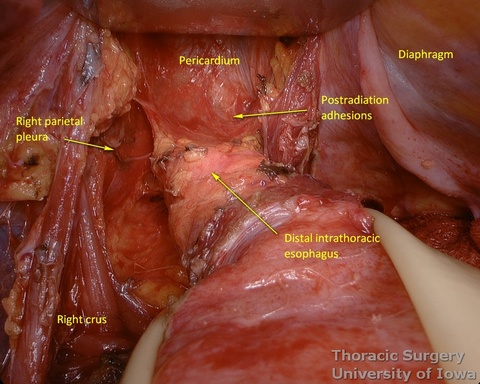

- The mediastinum is entered with the combination of sharp and blunt dissection. Note that postradiation adhesions become denser 4-6 weeks after neoadjuvant treatment.

- Once the mediastinum entered, the manual palpation through the hiatus is performed to assess mobility of the esophagus. Tumor is “rocked” from side to side to make sure it is not adherent to the aorta, prevertebral fascia, or mediastinal structures, thus assuring the feasibility of transhiatal approach or the need to perform transthoracic dissection. This should also be planned based on preoperative imaging.

- The illuminated transhiatal retractor is advanced into posterior mediastinum under direct vision

- The distal thoracic esophagus is visualized.

- Esophagus is circumferentially mobilized under direct vision using combination of sharp and blunt dissection up to the level of the carina.

- Right lateral esophageal “ligament” (attachments to the parietale pleura, pulmonary ligaments and branches of vagal nerves) is exposed are divided under direct vision

- Left lateral esophageal attachments (“ligament") is divided under direct vision

- Aorto-pleural and aorto-esophageal ligaments divide posterior mediastinum into peri-esophageal and peri-aortic (thoracic duct and azygos vein) compartments. They may be distinctly seen in some patients.

- Esophageal arteries (aorto-esophageal branches) and vagal nerves are divided under direct vision using the energy device.

- Periesophageal and subcarinal lymph nodes are dissected separately or en-block with the esophagus under direct vision.

- Use of energy devices should be limited near the membranous portions of the airways.

- Dissection of the distal and mid esophagus is completed using a combination of an energy device and suction tips.